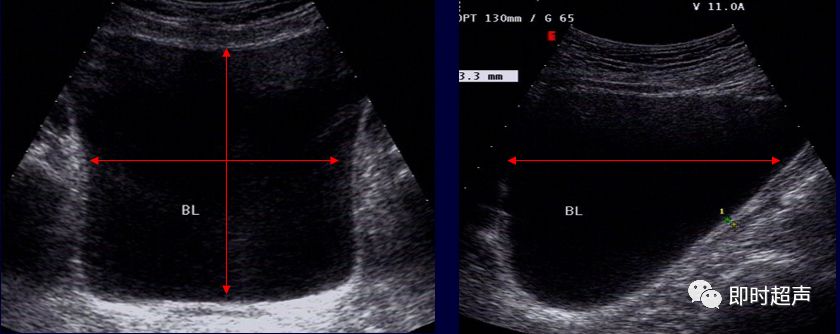

膀胱容量及残余尿量测定

测量方法:测量最大横切面的横径d1,厚径d2,以腹中线纵切面测d3。

残余尿量计算公式:0.5d1×d2×d3

残尿量是指排尿后,膀胱内未能排出的残余尿量。

对于少量残余尿测定可采用V=0.7d1d2d3公式可能更准确些。